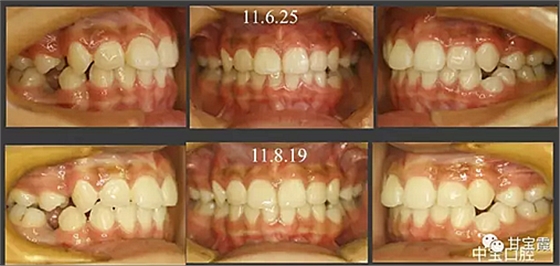

經(jīng)過三年零九個月的看護(hù),最終戴上了固定矯治器,但是大家不難發(fā)現(xiàn),孩子的牙齒已經(jīng)排齊,上下中線也基本對齊,面型也好看多了,這樣矯正就變得簡單,療程自然縮短,孩子也不遭罪了。

這個故事告訴我們,只有家長早點把孩子帶給正畸醫(yī)生檢查,才能早期發(fā)現(xiàn)早期治療。起到了事半功倍的效果。矯正以后還不容易復(fù)發(fā),因為從08年的初診到11年戴矯正器這三年多的時間里,孩子的牙齒是自己長好的。